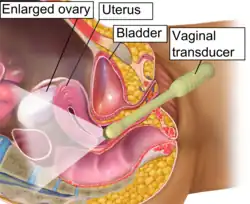

Vaginal ultrasonography in the sagittal plane in a woman with mild OHSS, showing a 33 mm wide anechogenic area behind the uterus in the recto-uterine pouch, which means there was ascites, that is, free fluid in the peritoneal cavity. Normally, there is up to 5 ml of fluid in the recto-uterine pouch,[5] corresponding approximately to an area up to 10 mm wide. The ovary measured up to 6.5 cm in diameter. |